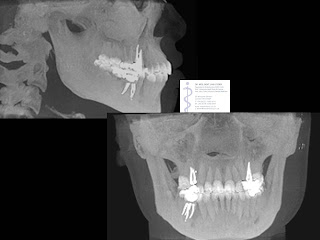

created for education and demonstration purposes